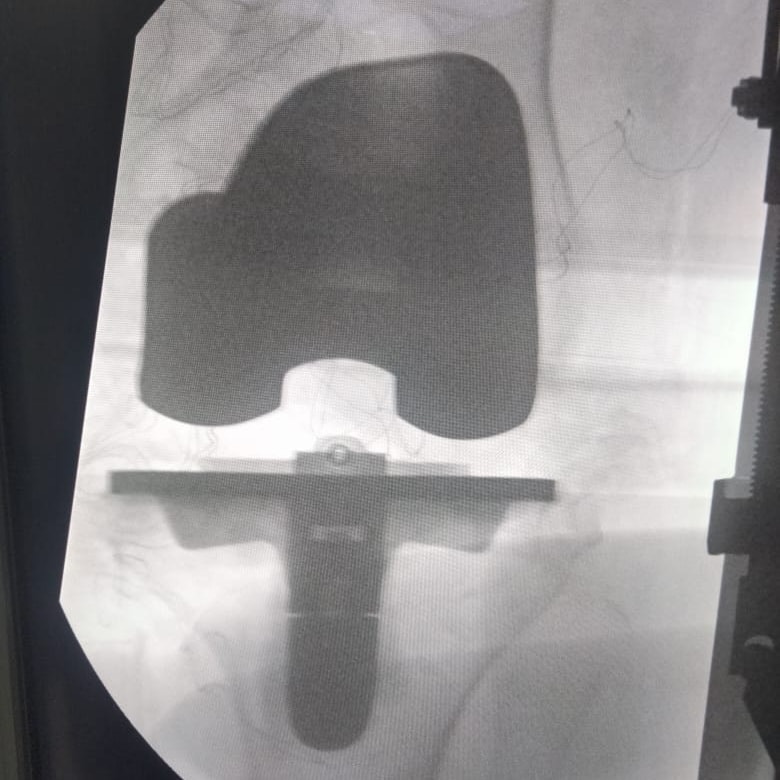

وكشف الدكتور كامل خالد مدير مستشفى قها التخصصي، أنه في إنجاز جديد لقسم العظام بمستشفى قها التخصصي، استقبل قسم العظام مريضة تبلغ 71 عام، وتعاني من آلام حادة وخشونة متقدمة بمفصل الركبة لدرجة تمنعها من الحركة تماما، مما أدى إلى تيبس بالمفصل، وعليه تم استقبال الحالة وعمل الفحوصات والأشعات اللازمة وعرضها على الفريق الطبي واستشاري جراحة العظام والمفاصل، وتم اتخاذ القرار بعمل عملية تغيير مفصل الركبة بمفصل كامل صناعي أسمنتي.

مفصل الركبة